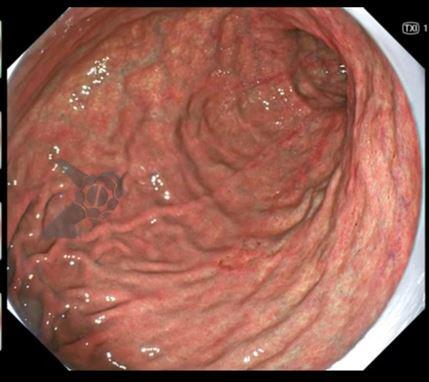

1. TXI (TeXture and color enhancement Imaging)

O TXI é uma tecnologia de imagem realçada. Basicamente, o que o sistema faz é processar a imagem com luz branca após a captura, melhorando sua nitidez. Primeiramente, a imagem capturada é dividida em dois componentes (textura e cor); depois, cada componente é realçado e então a processadora as une de novo e entrega uma imagem com mais qualidade. O resultado é um aumento da claridade nas partes escuras, assim como uma maior nitidez das cores.

Existem dois modos:

TX 1: realça tanto a cor quanto a estrutura.

TX 2: realça basicamente só a textura.

Fonte: Osaka International Cancer Institute.